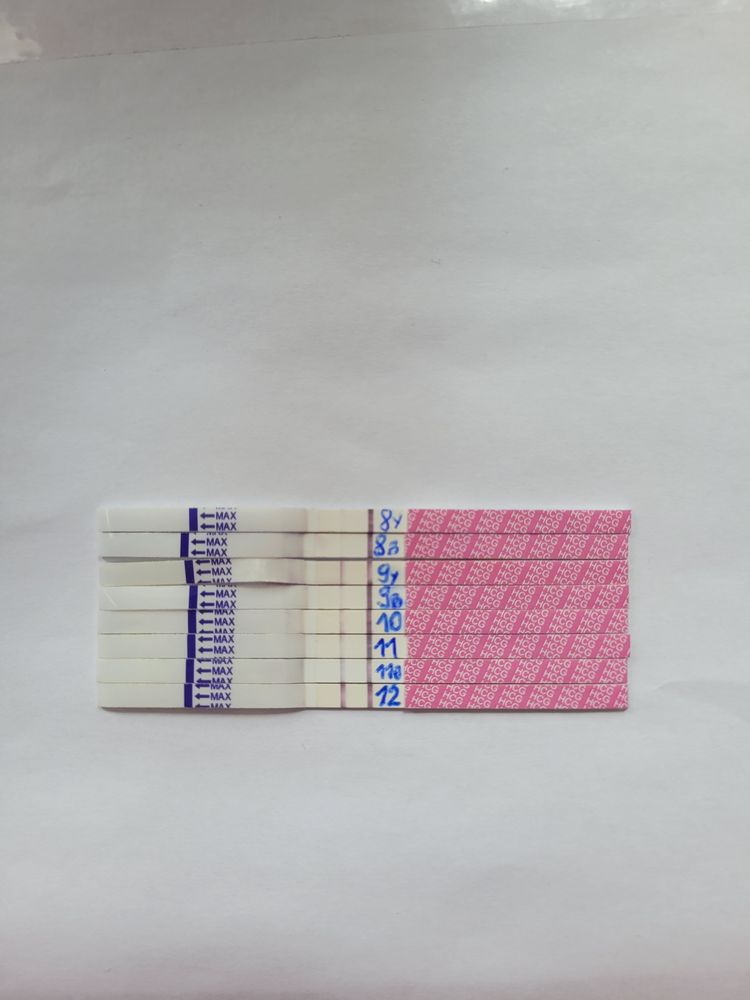

С 8 дпп начинаю делать тесты одной фирмы, тесты зебра, показывают,что и как хотят,тесты хорошие,поэтому не верьте тестам,верьте только хгч!

На 9 дпп сдаю- хгч 128.

10 дпп плановое-240

14 дпп - 1762

18 дпп - 6000.